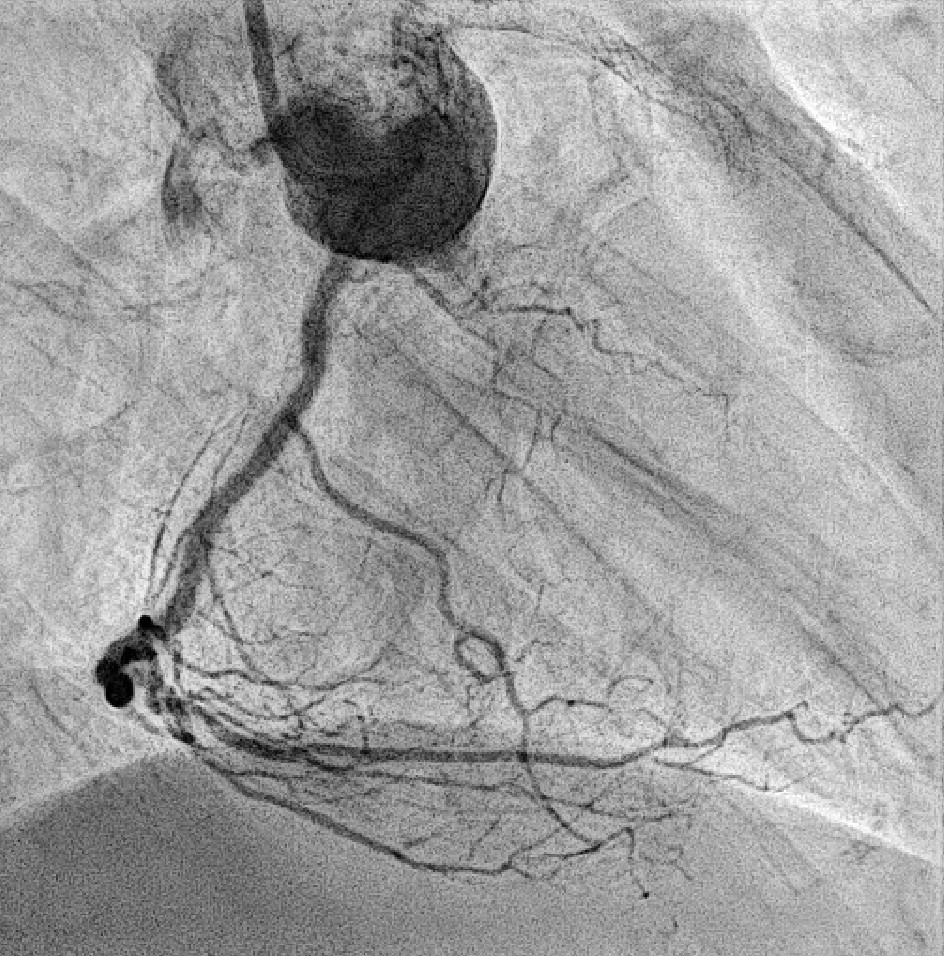

Coronary angiography revealed 81% in-stent restenosis at the right coronary artery ostium, worsened since February 2025. Proximal and mid RCA stents were patent; distal RCA was patent but smaller in caliber . Left main and LAD stents showed no progression, though 30–60% restenosis was seen in proximal to mid LAD. Left circumflex artery was nearly totally occluded from ostium to proximal segment, with preserved flow in mid and distal segments, similar to prior study.

We advanced a 6F JR 4.0 SH 100cm guiding catheter and crossed the RCA ostial lesion using a Fielder FC guidewire. Pre-dilatation was performed with Ryurei 1.5¡¿15mm balloon. IVUS was then performed, revealing a patent stent in the proximal to mid RCA. However, the ostial RCA stent was under-expanded, with smooth muscle compressing the stent from outside. Balloon pre-dilatation was carried out using an NC Euphora 4.0¡¿12mm balloon, inflated up to 22 bar. However, the lesion was resistant and could not be fully dilated. We then applied a 4.0mm intravascular lithotripsy balloon with a total of 100 shocks delivered. But the effect was still minimal. The IVUS showed limited additional plaque fracture or vessel expansion. We tried NC Sapphire II 4.5¡¿8 mm balloon inflation to 18 bar, but it was ineffective due to balloon slippage. The angiogram after oversized NC dilation showed residual stenosis of 59%. We then selected a Wolverine Cutting Balloon 4.0¡¿10 mm and initiated dilation to 6 bar, which resulted in easy slippage again. Subsequent oversized dilations were performed at 18 bar, after which the lesion was successfully dilated. Using a Runthrough Floppy guidewire with the floating wire technique, a drug-eluting stent Biofreedom Ultra 4.0¡¿14 mm was deployed in the ostial RCA ISR. We inflated at 14 bar for 14 seconds, repeated twice. Final post-dilatation was performed with an Accuforce 4.0¡¿15mm balloon. The final IVUS showed good stent placement and expansion. We closed the procedure.